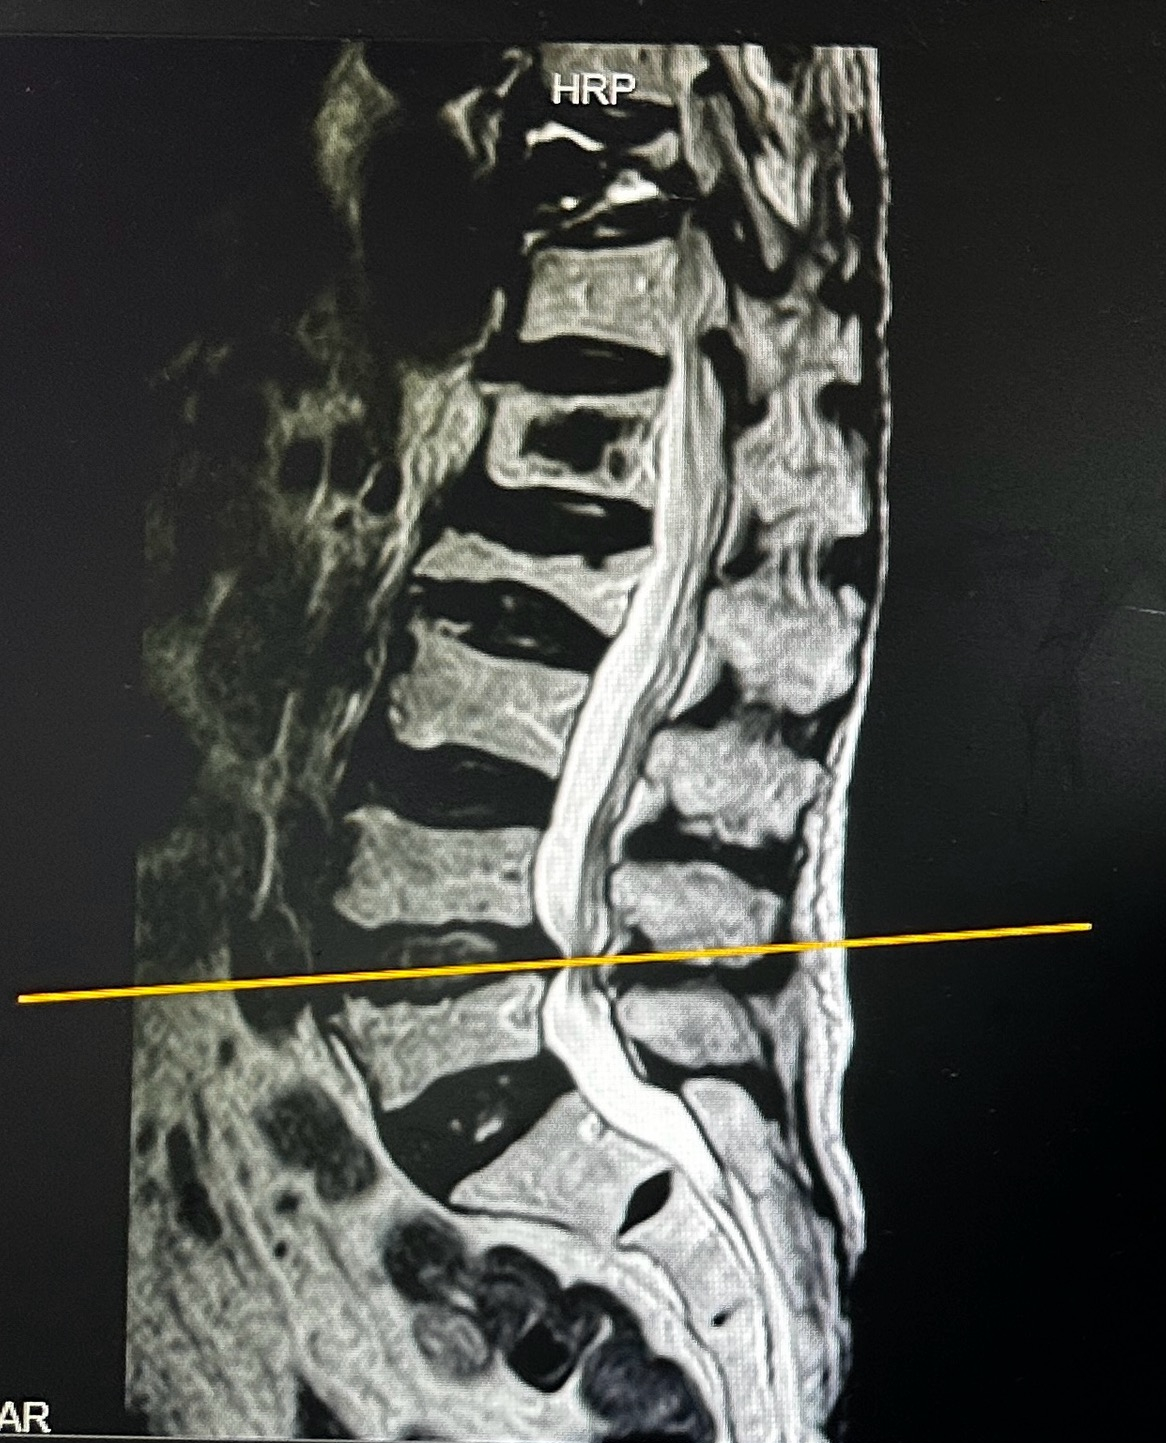

术前MRI片:严重腰椎椎管狭窄

我院副院长、骨科主任张勇华及省人医帮扶专家陈崇博士充分讨论病情后,考虑到徐婆婆为高龄老人,身体条件较差,同时合并腔隙性脑梗、高血压、重度骨质疏松、心肺功能异常等内科疾病,常规开放手术围术期风险较大,患者也不接受开放手术,采用脊柱内镜进行微创减压是非常好的治疗选择。